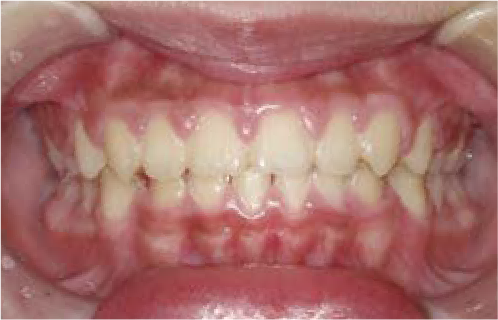

Nさん (矯正開始時:8歳)

Before

After

上あごの成長が少なく、特に前歯のガタガタが目立っていました。口呼吸のクセや飲み込み方に良くないクセが確認されました。

治療を終えて

マイオブレイスとBB1装置で上あごの成長を助け、鼻呼吸や正しい飲み込み方を身につけることで、きれいな歯並びとしっかり噛めるお口に変わっていきました。

姿勢やお口の機能を正しく整えたので、後戻りしない綺麗な歯並びを維持できています。もちろん非抜歯です。

主訴・治療内容 当院と交流のある歯科医師の先生が、ご自身のお子さまの治療を任せてくださいました。

「難しい歯並びでも永久歯を抜かず、全身の健康と顔立ちも考えて治療してくれる」と信頼していただいて治療開始。

治療期間 3年

費用 462,000円(税込)